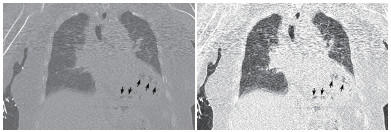

患者女性,75岁。因“被发现晕倒在地伴大小便失禁6 h余”于2018年10月25日12:10入院。患者为独居老人,当晚失联,入院6 h前,家人在家中发现其神志不清,大小便失禁,卧于床边,后患者家属呼120送至本院急诊科。入院后详细追问病史,患者身边无药瓶,家中亦无煤烟味。既往有“冠心病陈旧性心肌梗死、高血压病、2型糖尿病”病史11年余,“卵巢癌术后放化疗”病史2年余,“直肠占位”病史半年余。入院急诊体格检查:体温36.0℃,脉搏80次/min,呼吸17次/min,血压108/52 mmHg(1 mmHg=0.133 kPa),老年女性,神志不清,烦躁,面色苍白,皮肤湿冷、散在花斑,皮肤黏膜无破损。双侧瞳孔等大等圆,对光反射存在,言语、伸舌及肌力检查不合作,双肺呼吸音清,未闻及干湿性啰音,心率80次/min,律齐,心脏各瓣膜听诊区未闻及杂音,肝脾肋下未及,双下肢无水肿,四肢可见不自主活动,双侧病理征未引出。入院后心电图提示肢体导联及胸导联均有T波低平或倒置,V4-V6导联ST段压低(图 1)。血常规:白细胞计数32.35×109/L,中性粒细胞比率84.7%,中性粒细胞计数27.4×109/L,血红蛋白64 g/L,血小板计数221×109/L;CRP 111.9 mg/L,PCT > 100 ng/mL;肌酸激酶1 847 U/L,肌酸激酶同工酶356 U/L,肌酐219 μmol/L,肌钙蛋白T 6 257 pg/mL,NT-proBNP > 35 000 pg/mL。入院后急查颅脑、胸部及全腹CT,胸部CT提示左心室、室间隔及肺动脉根部区域见不规则条状、条片状低密度影,参考CT值约-200~-900 HU(气体密度影),外周伴伪影,左心室为著,外周分布为主,似累及心肌区域,部分心肌变薄,心包区域尚连续,主动脉系统未见气体影(图 2~3)。12:45患者病情急剧进展,呼吸心搏骤停,予气管插管、心肺复苏及药物抢救治疗,13:25抢救无效临床死亡,患者家属拒绝尸检。

| 示左心室、室间隔见不规则条状、条片状低密度影,参考CT值约-200~-900 HU,提示为气体影,左心室为著,外周分布为主,似累及心肌区域,部分心肌变薄,心包区域尚连续(白色箭头所示) 图 2 患者胸部CT结果 |

| 示气体影以左心室为著,外周分布为主,似累及心肌区域,部分心肌变薄(黑色箭头所示) 图 3 患者胸部CT冠状位影像 |

本例患者恶性肿瘤、糖尿病病史等使患者免疫功能低下,易合并重症急性感染。胸部CT显示左心室、室间隔及肺动脉根部区域见不规则条状、条片状低密度影,测量CT值提示为气体密度影。2016年Laiq等[1]曾报道因感染性心内膜炎致患者左心室内气体形成一例,患者血培养提示柠檬酸杆菌生长,最终患者发生急性心力衰竭,紧急二尖瓣置换术,术后乳头组织同样培养出柠檬酸杆菌,经抗感染治疗预后良好。2014年Alladina等[2]也曾报道一例因播散性肺克雷伯杆菌感染、产气,气体进入血液系统引起的脑空气栓塞。另外,临床工作中某些有创诊疗中,如深静脉置管、肺穿刺活检等也可能引起心脏空气栓塞[3-4]。但本例报道患者脑动脉、主动脉等大动脉系统未见明显气体影,说明患者左心室内气体不具有流动性。仔细观察胸部CT影像学表现,气体在左心室内主要沿室壁分布,部分心肌壁变薄,综合考虑为左室心内膜炎可能。左室内气体位于心内膜下,不在心腔内,故不具备游走性,这也就能解释为何患者其他动脉系统血管内不存在气体的原因。